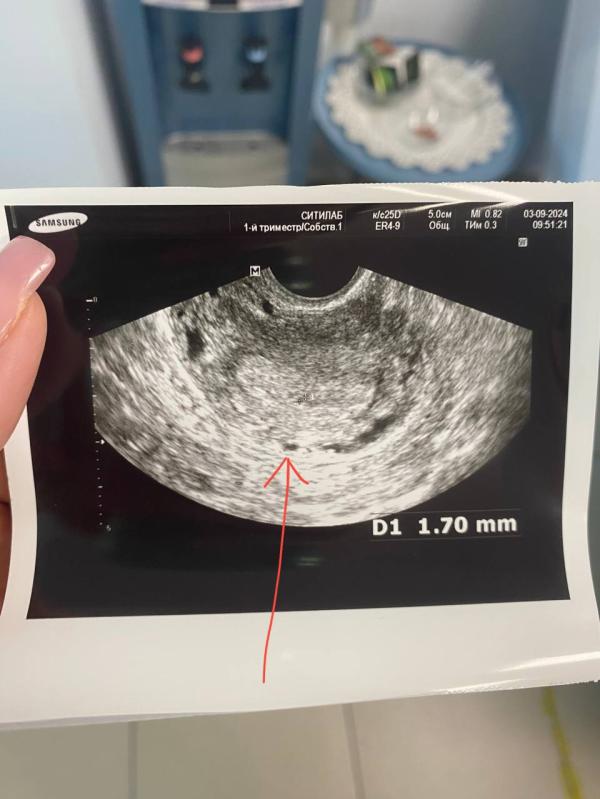

Нашла малюсенькую точку почти в 2 мм, фактически подтвердила беременность,так как сказала другое это ничего быть не может ,но на бумаге она пока это подтвердить не может ,из-за недостаточного размера 🤞🏻